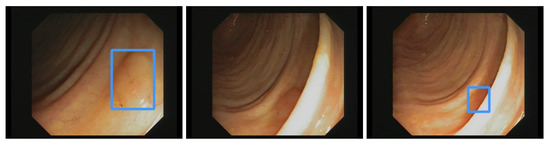

where X denotes the old pixel value, X s c (X scaled) the new pixel value, X min the minimum pixel value of the image, X max the maximum pixel value of the image. After normalization, we apply data augmentation. In deep learning, augmenting image data means modifying the original image data by using various processes. We are applying the augmentation displayed in Figure 3. The most basic augmentation we apply is flip augmentation. This is well suited for polyps as the endoscope can easily rotate during colonoscopy. Here, the image is flipped horizontally, vertically, or both. We applied a probability of 0.3 for up and down flips and a vertical flipping probability of 0.5. We additionally apply rescaling to the image with a probability of 0.638. Rescaling creates polyps in different sizes, adding additional data to our dataset. The translation moves the image along the horizontal axis. Furthermore, we applied a low probability of 0.1 to rotate the image with a randomly created degree. For example, 20-degree rotation clockwise. As the last augmentation, we apply mosaic data augmentation. Mosaic data augmentation mixes up to four images into one image. In this implementation images can not overlap. Thereby, the image is rescaled, causing the images to appear in a different context. Mosaic data augmentation is applied with a probability of 0.944. These data augmentations are only applied to the training data. All of the hyperparameters for these augmentations are chosen by the parameter optimization of the genetic algorithm which is further illustrated in the hyperparameter optimization subsection below. All of the augmentations are combined to create new training images.